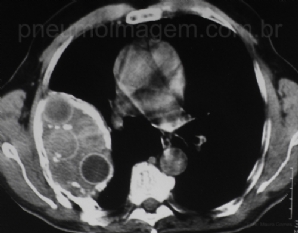

CASO CLÍNICO #4

Paciente do sexo masculino, 69 anos, assintomático, encaminhado devido ao achado tomográfico. Nega tabagismo. Refere tratamento para tuberculose 50 anos atrás. Ao exame apresenta deformidade torácica, escoliose, com ausculta pulmonar com MV reduzido em terço s...